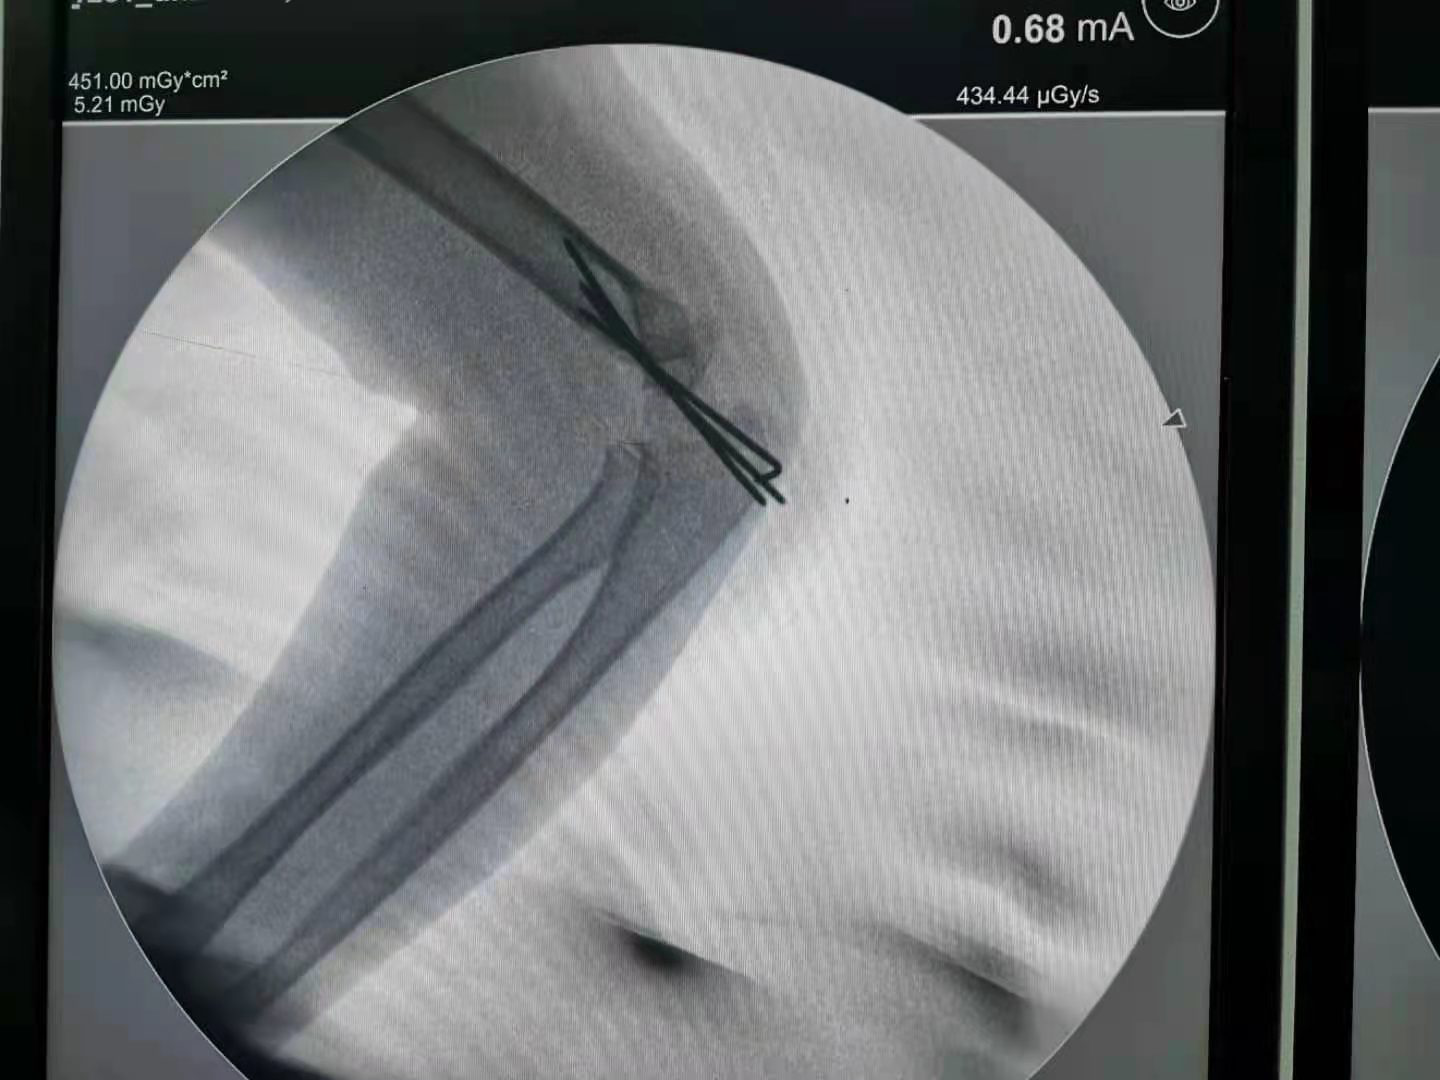

为了不断地满足患者的美观需求,同时医疗技术的不断提高,不需开刀不留瘢痕治疗儿童肱骨髁上骨折不再是梦。对于肱骨髁上骨折,我们的手术方法是“闭合复位经皮穿针固定”,是先进的微创手术方法,绝大多数不需要开刀,损伤很小,没有切口也不会留下瘢痕。只有非常少的情况下,例如开放性骨折或者骨折不可复位才可能需要做切开复位。